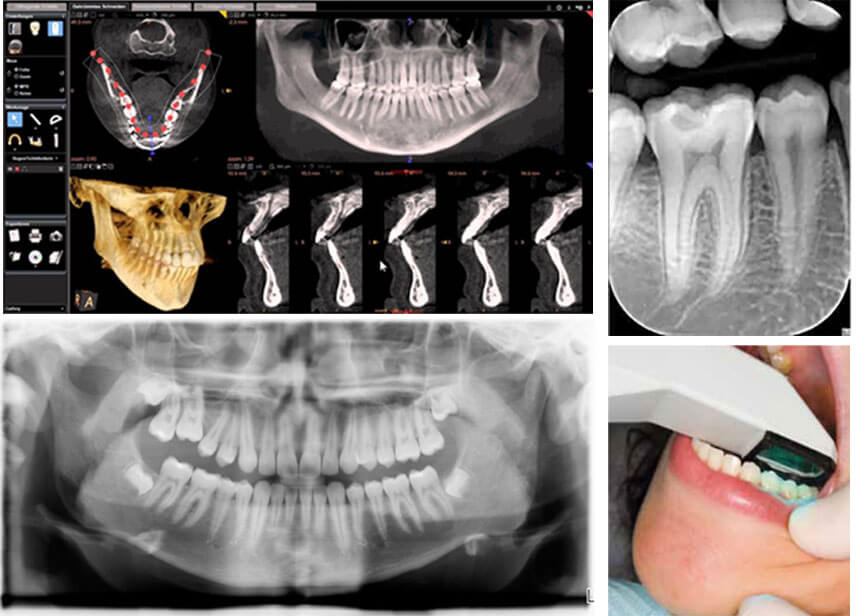

In modern day dentistry, almost every procedure can be digitized; right from caries diagnosis, to radiography, to laboratory communication, to intra- and extra-oral imaging, to smile designing, shade matching, planning implant surgeries, and even basic practice management; all can be accomplished by the various available technological advancements in dentistry.